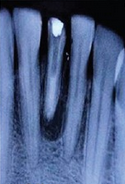

诊断为41牙慢性根尖周脓肿。首先取出41牙根管内尖锐物体,其次完善根管治疗,进行根尖手术,控制根尖周炎症。

病例中患者幼时受到外伤后未及时诊治,而且在疼痛时往根管内放置尖锐物体,进而导致严重的根尖周炎症。由于根管内的异物能够通过疏通取出,故而未利用超声系统。患牙根尖孔尚未愈合,根管粗大,整个治疗过程中要尽量保存剩余牙体组织,修复时也选择与牙本质弹性模量相近的纤维桩进行修复。